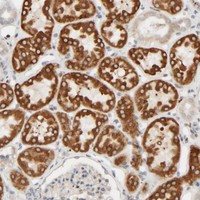

Immunohistochemical staining of human kidney shows strong cytoplasmic positivity in renal tubules.